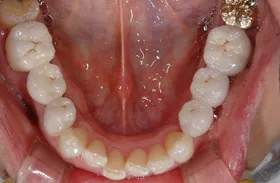

■治療前:生まれつき下顎左右前歯がなく隙間がある

■治療後:矯正治療後、下顎左右3番の2本にインプラント治療

| 主訴 | 生まれつき歯がなく隙間があり、審美障害・咀嚼機能障害がある |

| 治療方法 | インプラント治療 + 矯正治療 |

| 治療期間 | インプラント治療 約6ヶ月 |

| 通院回数等 | インプラント治療 約6回 |

| 費用 | 約94万円(税込) |

| リスク・副作用 | 術後の腫れ・痛み |